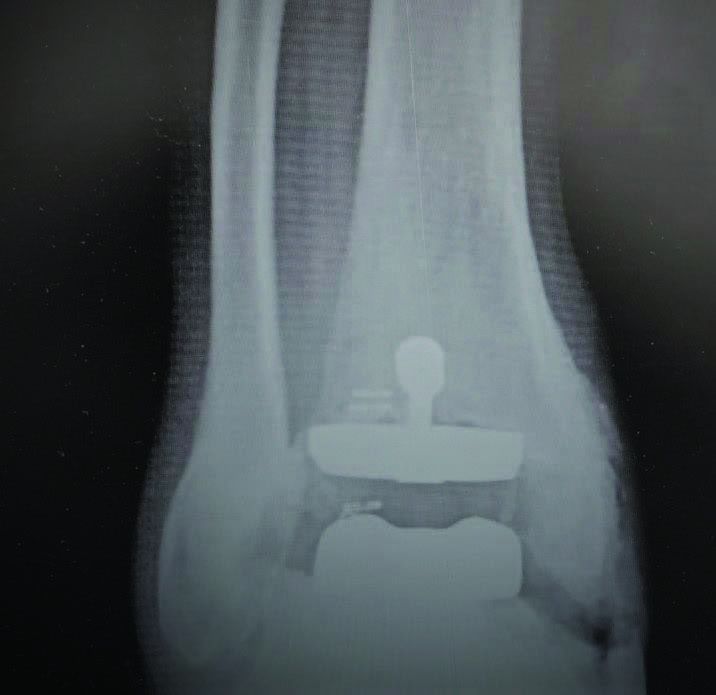

- Joint fusion using plates, screws, or rods

- Minimally invasive fusion techniques, where possible

- Reconstruction of severely damaged joints

What imaging tests are needed before the surgery?

X-rays, CT scans, or MRI are used to understand the damage and plan the surgery with precision.